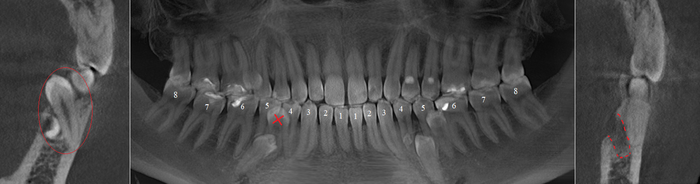

Фрагмент компьютерной томографии (вид сбоку):

Контрольная ортопантомограмма:

Прицельный снимок:

Я согласен, что эстетика хромает. Давно пора менять временную коронку на постоянную, что улучшит результат. Но, как я говорил, все упирается в финансы.